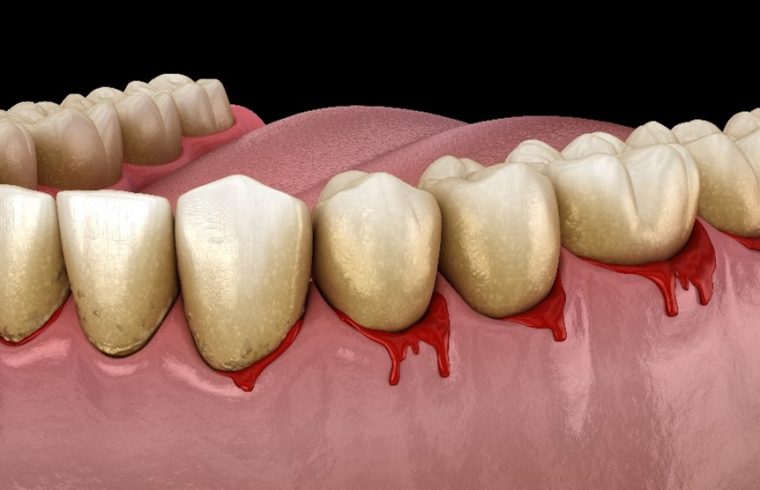

歯ぐきから出血をしているイメージイラスト

歯周病とは、歯と歯ぐき周りの組織に炎症が起こる慢性的な口腔疾患の一つです。歯周組織が炎症を起こし、歯の周りの歯ぐきや歯を支えている骨が溶けてしまう病気です。進行すると歯と歯ぐきの間に深い溝(歯周ポケット)ができます。歯周ポケットの中で細菌が増殖し、歯周病はさらに悪化します。

細菌が食べかすなどを分解する過程で強い臭いがするガスが発生するため、口臭の原因にもなります。

1. 歯ぐきが腫れ上がり、赤くなる

2. 歯磨きや食事の際、歯ぐきから出血がある

3. 歯ぐきを押すと血や膿が出る